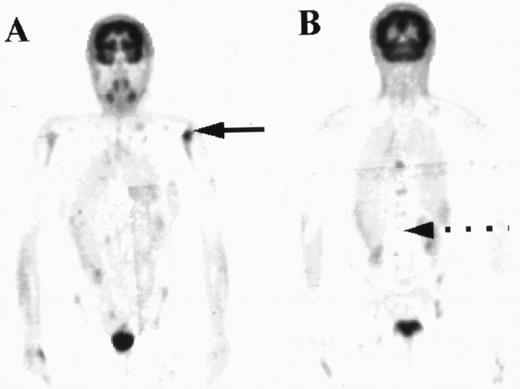

For the purposes of this study, the intensity and distribution of FDG activity within the marrow was visually scored by three nuclear medicine physicians independently. The marrow was assumed to be abnormal where the uptake was equal to or greater than uptake into the liver, provided the liver uptake was greater than background. In one patient where there was negligible uptake within the liver, marrow uptake was compared to uptake within soft tissue rather than using the liver as the reference organ. The pattern of increased uptake was also noted, with patients who appeared to have focal disease only within the marrow differentiated from those with diffusely abnormal marrow changes. Representative examples of cases with marrow uptake of differing intensity (Fig 1) and distribution (Fig 2) are shown.

Coronal images are shown from three patients with different degrees of marrow uptake on PET. FDG uptake within the marrow is seen on these sections in the thoracic spine (broken arrows) and within the liver (solid arrow). The intensity of uptake was graded as less than liver (A), equal to liver (B), or greater than liver (C), with the marrow deemed to be abnormal where uptake was equal to or greater than liver.